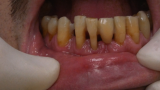

Jedną z popularniejszych metod stabilizacji zębów rozchwianych jest ich szynowanie. Metoda ta, wspierająca inne metody leczenia, jest powszechnie stosowana. Jednym z najnowocześniejszych materiałów wykorzystywanych w stomatologii do szynowania zębów jest taśma poliaramidowa. W opisanym przypadku autorzy pracy przedstawiają sposób uproszczenia całej procedury i ograniczenia ryzyka popełnienia błędu, szczególnie w sytuacji całkowitej utraty zęba. Uzyskano to dzięki zastosowaniu indeksu wykonanego z przezroczystego silikonu.

One of the more popular methods of stabilising loose teeth is to splint them. This method, aiding other methods of treatment, is generally used. One of the most modern materials used in dentistry for splinting teeth, is polyamide tape. In the case described the authors show how to simplify the whole procedure and limit the risk of making a mistake, particularly in the situation of total loss of one tooth. This was achieved thanks to the use of an index made out of transparent silicone.